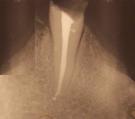

Una vez se ha realizado la limpieza y conformación, se procede al secado mediante puntas de papel y al cierre hermético y tridimensional de cada conducto. Esto se realiza mediante un material llamado "gutapercha",en forma de conos, usado universalmente en endodoncia. Previamente se debe comprobar radiográficamente la longitud y el ajuste del cono principal.

La técnica más extendida consiste en ir sellando el conducto mediante puntas de este material que ajustan a la longitud exacta del conducto (aproximadamente a medio milímetro del final), de esta manera se van aplicando una tras otra y presionando lateralmente hasta que el conducto se ha obturado completamente. Como agente de unión se emplea un cemento específico para endodoncia. Existen también otras técnicas donde la gutapercha se calienta y se compacta verticalmente.

Es muy importante que el conducto quede totalmente obturado a la longitud correcta (de 1 mm a 0,5 mm del final). El material no debe quedar a menos distancia ni pasarse de esta longitud para obtener las mayores posibilidades de éxito.